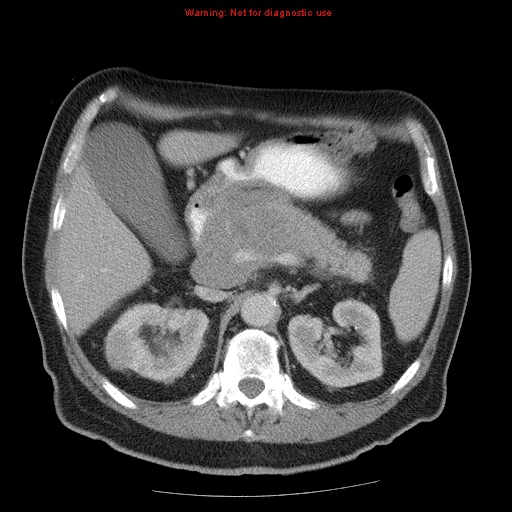

Ung thư biểu mô tế bào thận (Renal Cell Carcinoma - RCC)